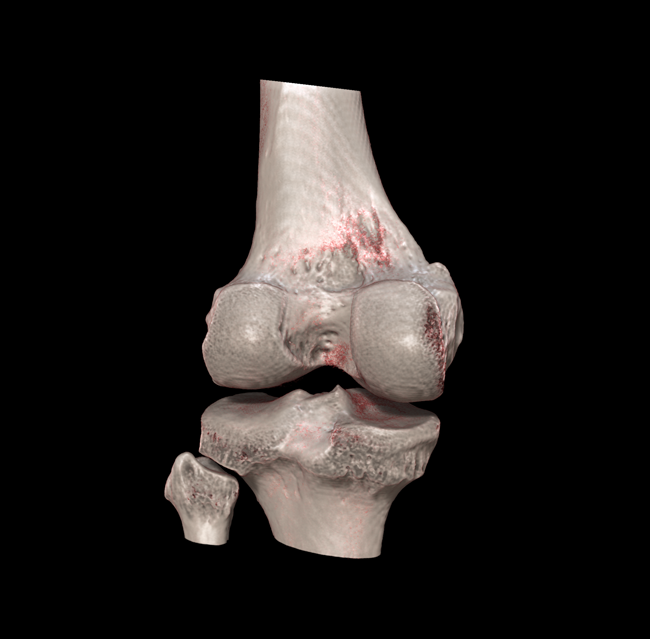

HRCT

High Resolution Computed Tomography. Outstanding image quality with a voxel size up to 100 µm